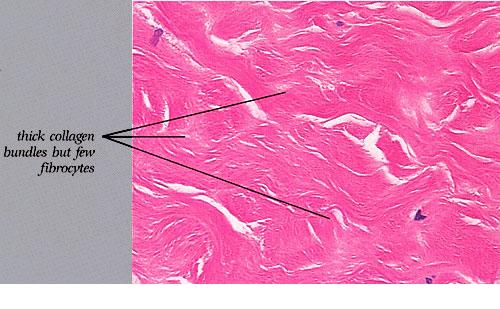

The dermis in scleredema is about three times thicker than normal . The collagen bundles are thickened and separated by clear spaces, causing "fenestration" of the collagen. The secretory coils of the sweat glands, surrounded by fat tissue, are located in the upper dermis or mid dermis rather than, as normally, in the lower dermis or at the junction of the dermis and the subcutaneous fat. Because the distance between the epidermis and the sweat glands is unchanged, it can be concluded that much of the subcutaneous fat in scleredema has been replaced by dense collagenous bundles . No increase in the number of fibroblasts is noted in association with the hyperplasia of the collagen; in fact, their number may be strikingly decreased .

|